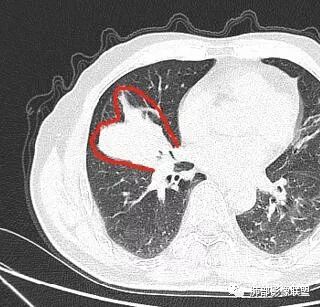

入院CT

老年男性,亚急性病程,咳嗽咳痰。右肺中叶团片影,外朝内分布,大部分边界清楚平直,内侧支气管进入,团片影见低密度坏死区,强化明显,延迟强化,血管破坏不明显,符合爬行征5个特点:

1.肺外周生长。

2.外侧部分体积大于内侧。

3.病变最大径与肺的纵轴及水平面任何一条轴线不平行。

4.病变内侧支气管通畅。

5.病变区域肺容积无缩小。

双侧肺门及纵隔淋巴肿大并可见钙化。考虑结核,但部分边缘膨隆,肿瘤待排。

老年男性,因“咳嗽咳痰1月余。”入院。病程中咳嗽咳痰,咳黄白痰,间断咯少许鲜红色痰血。PPD阳性。胸CT:右肺中叶外侧段支气管管腔阻塞,大片实性病变,病灶边缘光滑,部分边缘膨隆,可见分叶,肺门及纵隔可见肿大淋巴结,并可见钙化。增强可见病灶明显强化,而且延迟强化明显,病灶内多发低密度区,内见血管影,血管变细、部分血管破坏。考虑恶性病变可能性大,鉴别慢性肉芽肿性病变。

右肺中叶外侧段管腔阻塞、实性病变,病灶边缘光滑,可见分叶,肺门及纵隔可见肿大淋巴结,并可见钙化。增强可见病灶内多发低密度区。

老年男性,咳嗽、咳痰1月余,间断血痰。PPD阳性。

胸CT:跨叶大肿块,主体在中叶,右中叶外侧段支气管阻塞,病灶部分边缘膨隆,可见分叶,部分边缘平直,肺门及纵隔可见肿大淋巴结。增强病灶不均匀强化,延迟强化明显,病灶内多发低密度区,内见血管飘浮,部分血管变细、模糊。考虑:恶性病变可能性大,大细胞?淋巴瘤?鉴别慢性肉芽肿性病变。

右肺中叶软组织肿块,外围向内生长,叶间胸膜向前内移位,肿块近肺门侧跨叶,中叶外侧段支气管截断,密度不均匀,双侧肺门及隆突下见肿大淋巴结,增强后呈中度不均质强化,肺动脉供血,多发坏死区,边界尚清,坏死区域内见结构,结合病史考虑恶性,鉴别诊断1结核,爬行征是沿支气管树分布,外宽,内窄,周围有卫星灶,内气管狭窄后扩张,此例沿叶间胸膜长轴分布,气管有截断,不典型。2炎性肉芽肿,符合的地方下方层面增强后延迟性轻度环形强化,不符临床无发热等急性感染病史,实验室指标不符,病灶周围渗出及慢性炎性改变有,不明显。

主病灶在中叶,但是左肺舌段叶有条索影,陈旧病变。蓝色箭头支气管受压,是淋巴结肿大

主病灶在中叶,但是还有结节状病变在下叶

叶间裂推移方向

虽然是一个大的病灶,但是周围是比较散

这个支气管是走形通畅,但是壁增厚的。比较符合炎症改变

下面我们看看支气管都在吗?

内侧段是通畅但是受压的

外侧段一开始狭窄

但是远端通畅,所以我认为支气管都没有堵塞,不太可能是鳞癌

边缘还有多发小灶

淋巴结肿大,钙化。

但是钙化,密度高,没有融合,平扫没有坏死

病灶明显平直,中央是粘液栓,低密度,分界清楚

综上,考虑炎症,结核。